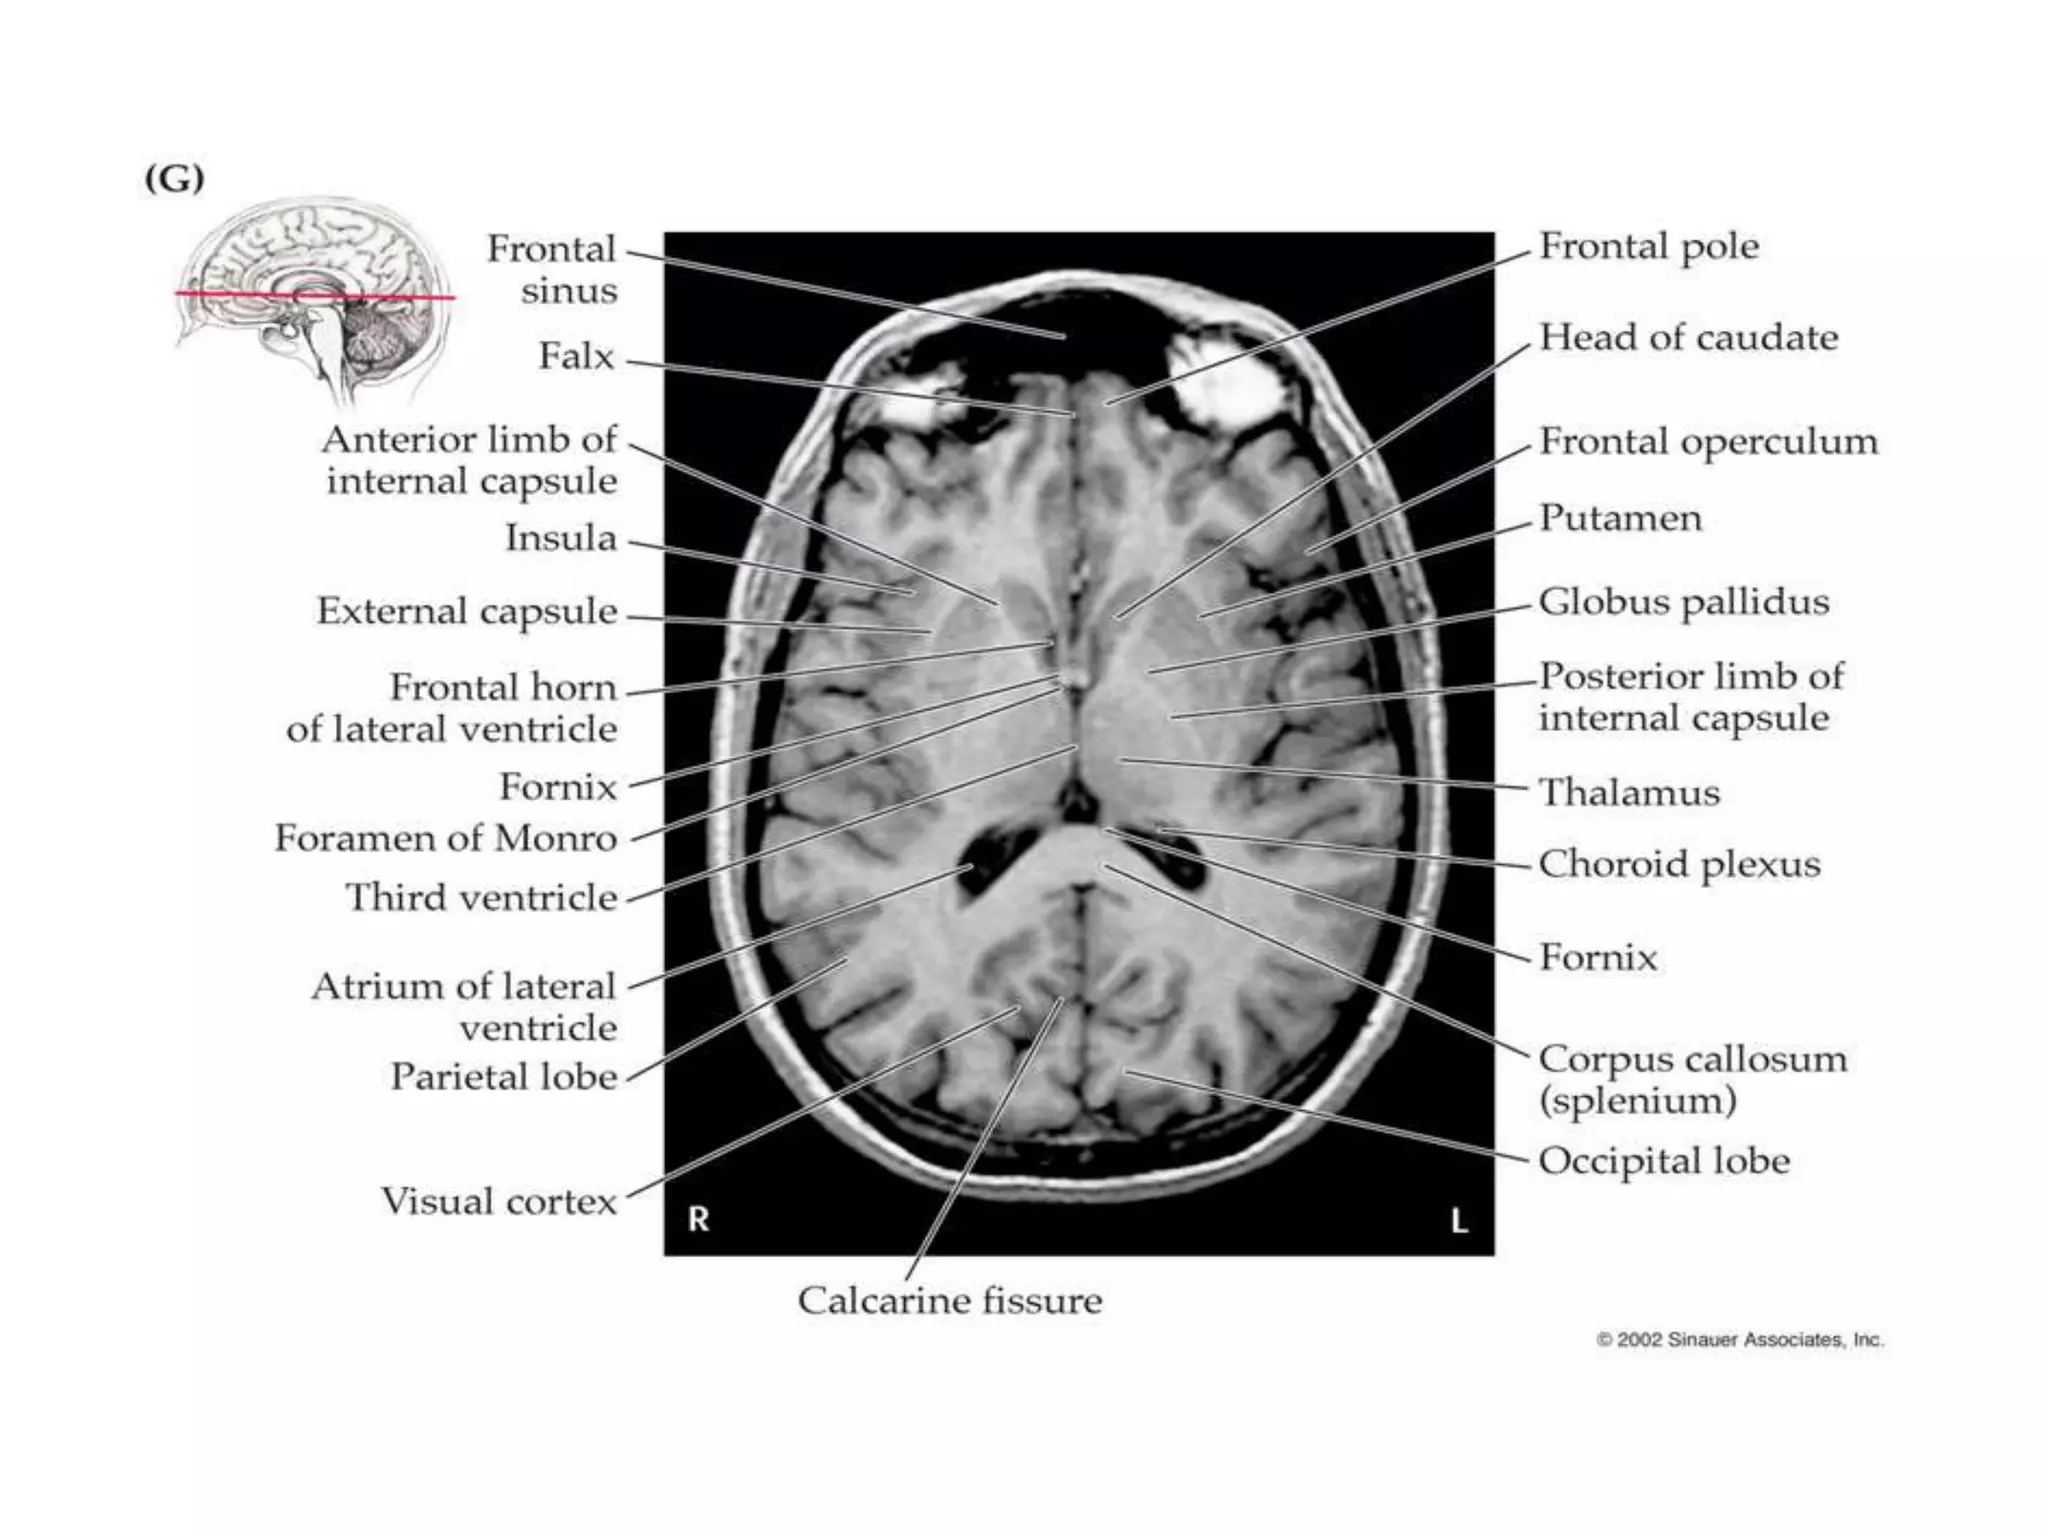

Coronal section of the cerebral hemispheres showing the position and relations of the thalamus.

Coronal section ofthe cerebral hemispheres showing the position and relations of the thalamus.